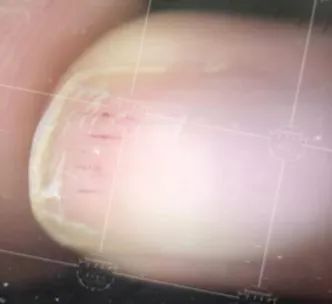

116人中有65个人都发生了甲脆裂,就是这样子:

2.甲层裂

有32个人出现了甲层裂,就是指甲分层,尤其喜欢去抠甲油胶的人,指甲的这个样子你们应该很熟悉了。